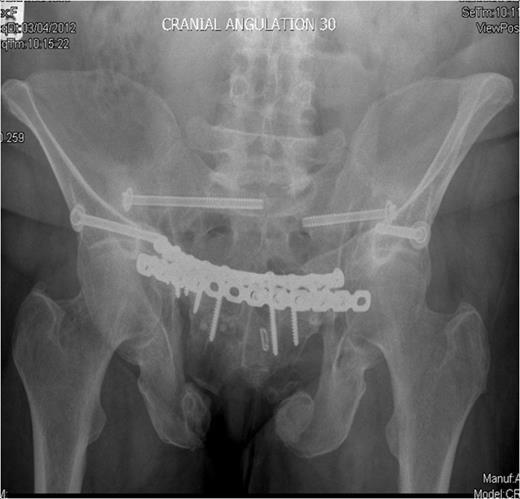

Post-operative recovery was uneventful. Bone and soft tissue biopsies showed no abnormalities. She was kept non weight bearing for 12 weeks. Subsequent dual energy X-ray absorptiometry scanning revealed mild osteopenia for which she is being managed medically. She began full weight bearing at 3 months post surgery. Final follow-up at 16 months demonstrated that the fractures had healed, and the patient was pain free and mobilising unaided (Fig. 3 & 4).

Outlet radiographs at 16 months post surgery demonstrating solid fixation and bony healing